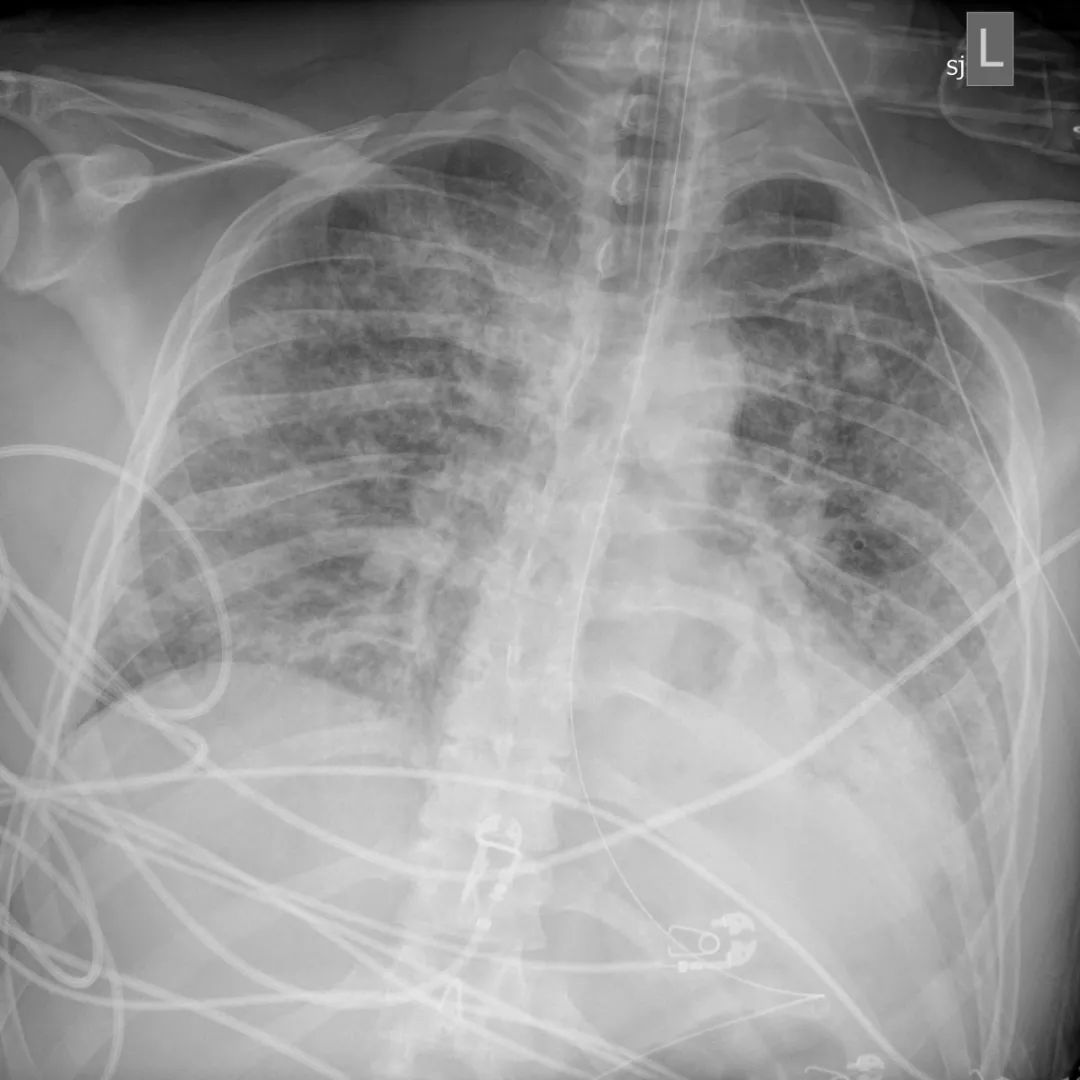

这是我见过最糟糕的胸片

在胸部拍片检查中,他的肺部看起来和旁边的骨头一样白,整个肺部已经没有了含气的地方(肺内实变之后含气量减少,密度增高,颜色变白),他的医生库里尔(Paul Currier)说:“这是我见过最糟糕的胸部拍片”。

3月14日,贝洛的第一张肺部X光,

肺部充满液体和炎性细胞

虽然医生已经放出了大绝招,但是贝洛胸片越来越糟。他第一次拍的胸片虽然显示出明显的积液和炎症,但还可以看出肺脏影像,3月18日,胸片所见恶化,但肺的轮廓仍然可见。到3月20日时,他的肺部表现基本上就是我们所说的“大白肺”(完全实变,肺影全部变白)